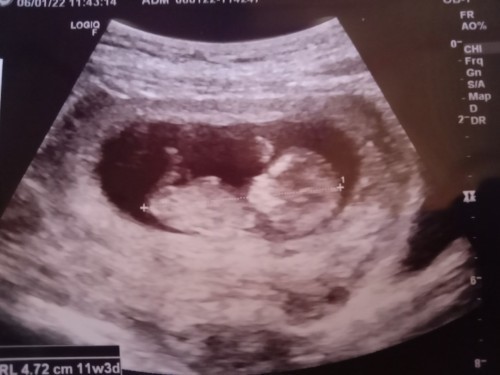

11วีค3วัน ตัวโตไปไหมคะแม่ๆ

ไม่ค่ะ หมอแค่ซูม อายุครรภ์เท่ากันเลยค่ะ แต่ของเรายาว 4.84 ยาวกว่าของแม่ในรูป แต่ของแม่ดูตัวใหญ่เพราะหมอซูมภาพ